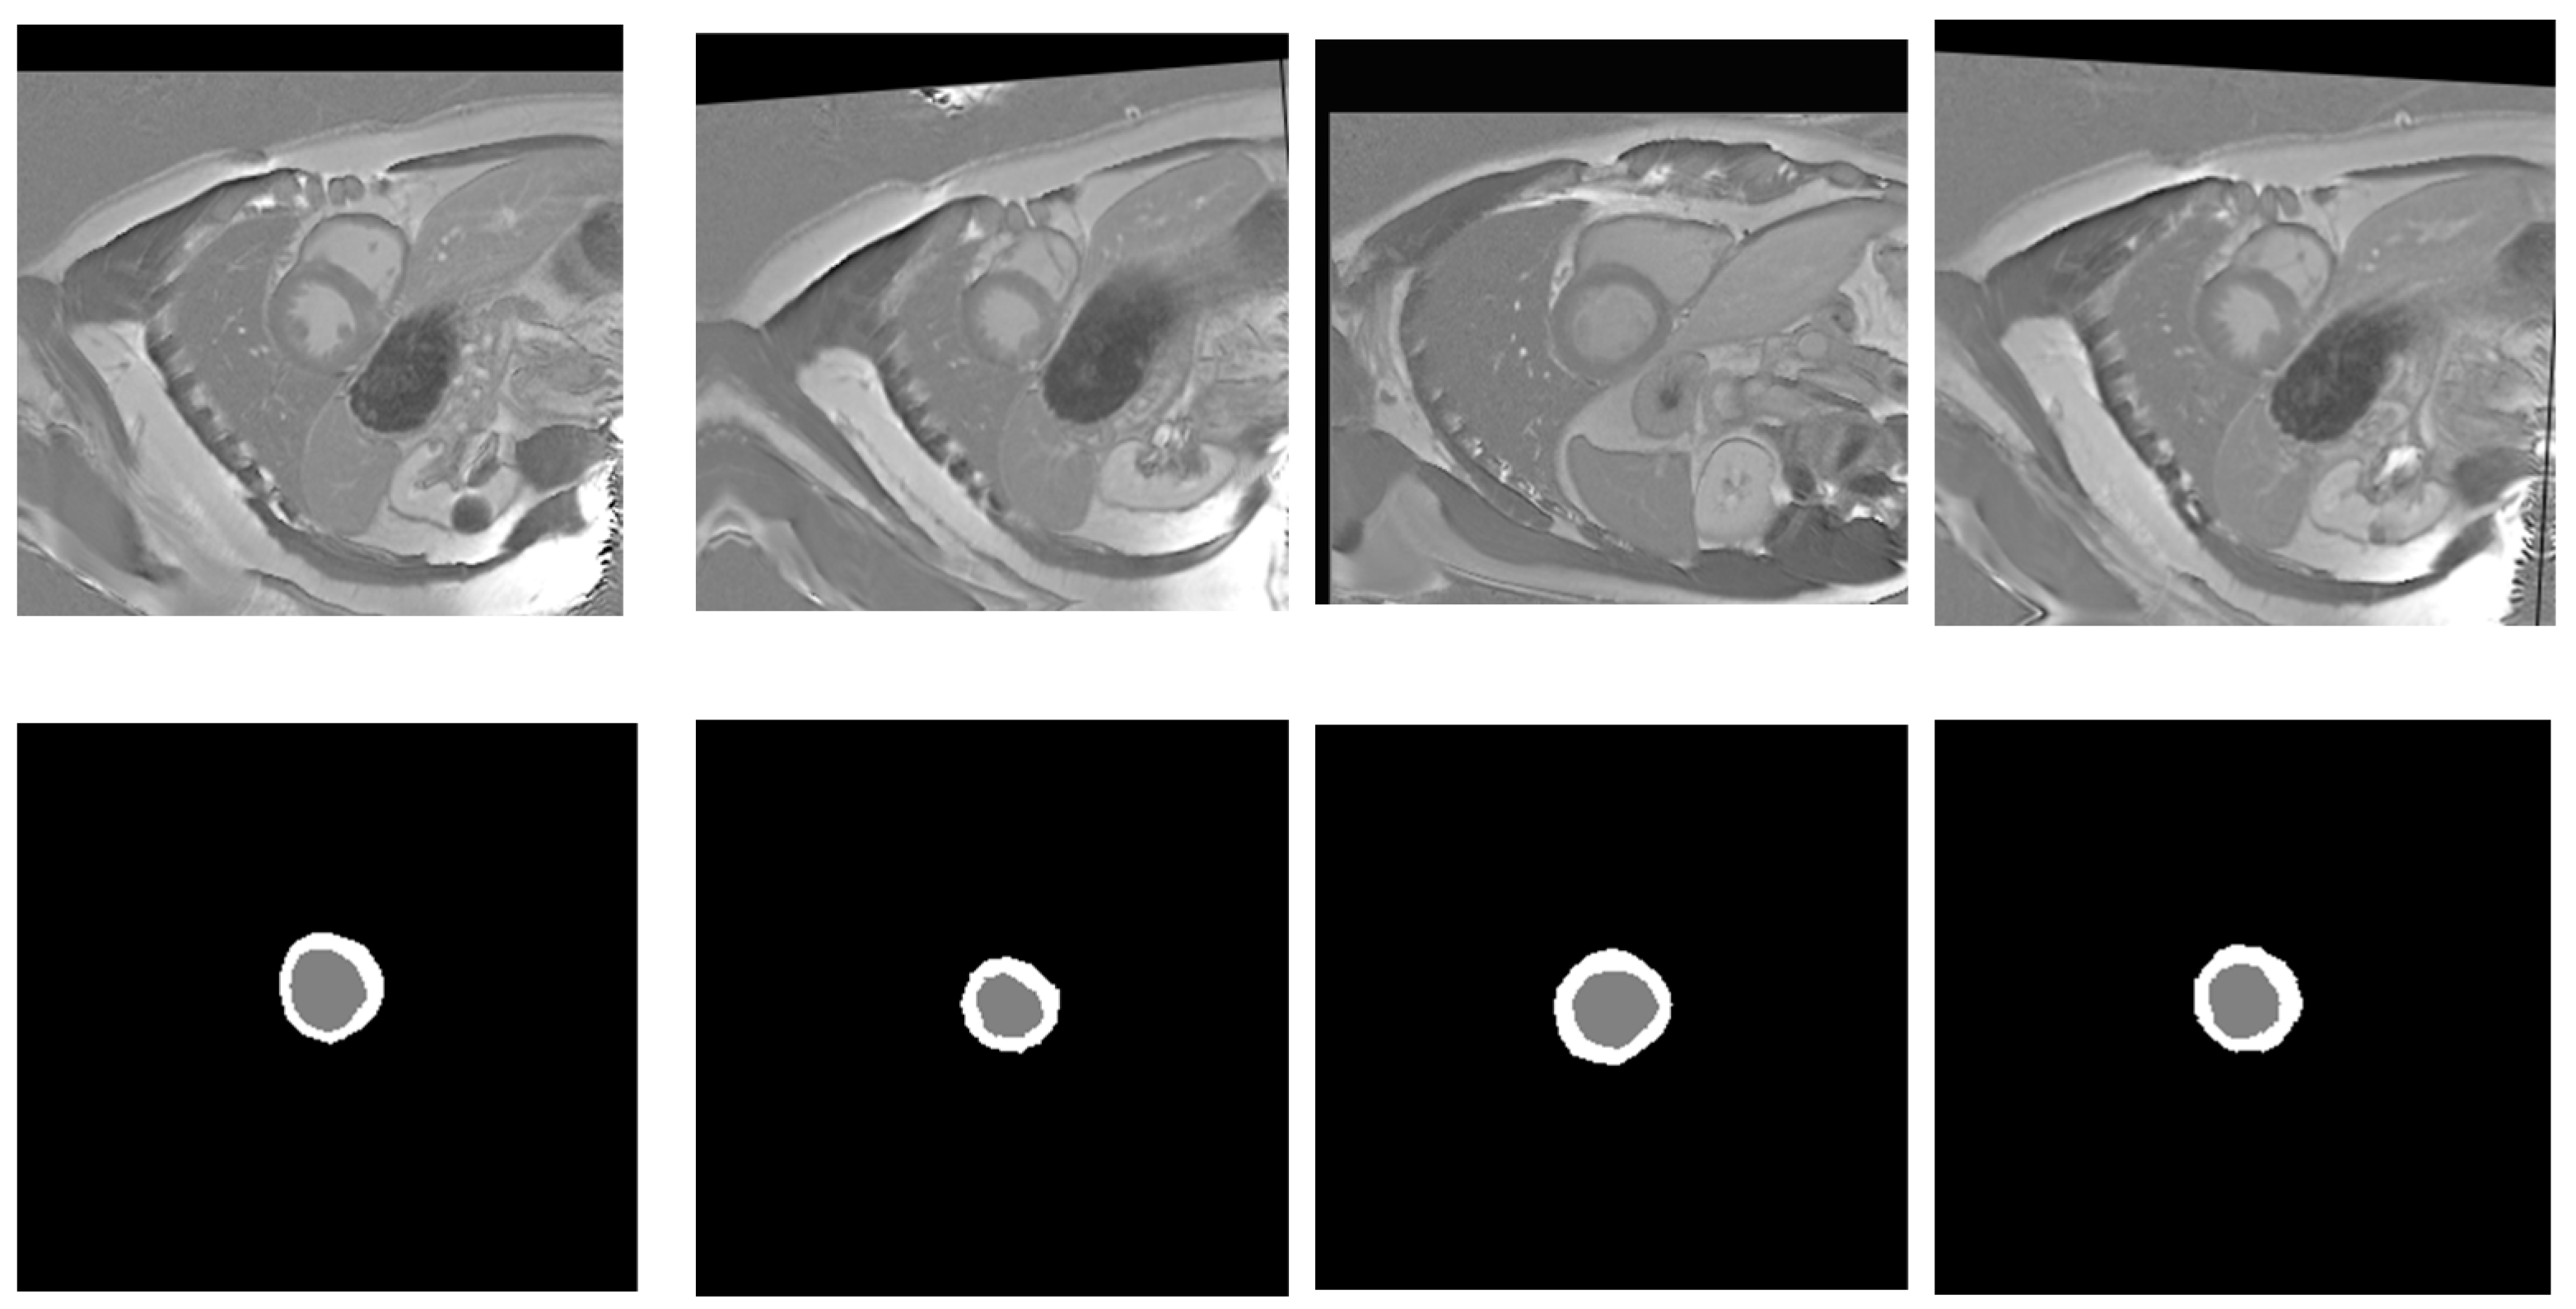

Image augmentation is widely used in computer vision to improve models’ performance and generalization, especially when there is limited training data. This technique also helps models learn under different lighting conditions, orientations, and background noise, making them more robust and reliable in real-world applications. Since the source training data contains only 33 normal cases with 235 original images, we applied data augmentation techniques [] to cardiac MRI images to augment the training data and improve the model training. It is a crucial step that allows us to increase the variety of data for training the model. To enhance the robustness and generalizability of the model while maintaining anatomical realism in cardiac MRI data, we adopted a carefully designed data augmentation strategy. A horizontal flip was applied with a probability of 0.5, introducing left–right symmetry without violating the anatomical integrity of the images. Mild rotations up to 5 degrees were allowed with a 30% chance to simulate natural variations in patient positioning during scanning. In addition, small-scale geometric transformations, including slight shifts (up to 3%) and zooms (up to 5%) combined with the same modest rotation limit, were applied with a 50% probability to introduce controlled spatial diversity. To simulate minor variations in scanner acquisition settings, subtle changes in brightness and contrast, limited to 5% in either direction, were introduced with a 30% probability. This augmentation setup prioritizes clinically plausible transformations, ensuring the anatomical consistency of cardiac structures while still promoting sufficient variation to aid in model generalization. These augmentation methods generate various images, which allows the model to learn under different conditions and enhances its generalization ability. This augmentation process results in generating 3000 images in total. Figure 3 shows different examples of augmented images with their corresponding masks.

Figure 3.

Random samples of augmented images (top row) alongside their ground truth labels (bottom row). Gray color denotes the LV, while white signifies the Myo.